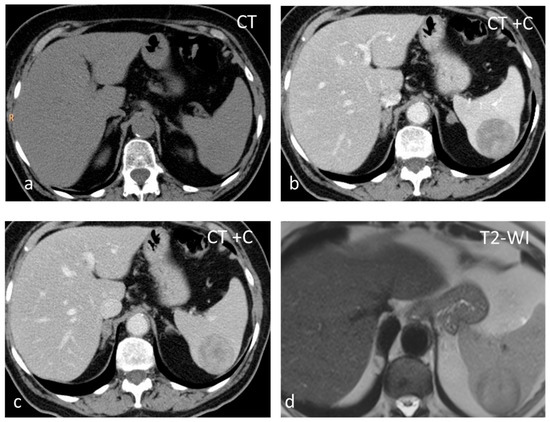

Inflammatory myofibroblastic tumor (IMT), formerly known as inflammatory pseudotumor, is an uncommon benign splenic lesion. It has been described in virtually all major organs with a few exceptions. In the liver and spleen, inflammatory pseudotumor is possibly linked to Epstein–Barr infection [13]. The prevalence is similar in both sexes, with a peak incidence in middle age. The lesions reported are usually large, measuring > 10 cm. It is composed of a combination of inflammatory and myofibroblastic spindle cells. Usually an incidental finding, it is included in the differential diagnosis of malignant splenic lesions, although currently, the World Health Organization classification of soft tissue tumors places IMTs in an intermediate category between benign and malignant, with metastases in less than 5% of extrasplenic cases [14,15]. In the US, inflammatory myofibroblastic tumors appear as solid hypoechoic masses. CT shows hypoattenuating hypoenhancing lesions, and stellate central calcifications seen on CT scans make the diagnosis very likely [16]. They present as hypointense masses both on T1-WI and T2-WI, with slow delayed enhancement (Figure 1) [17]. The diagnosis can be confirmed reliably only by histopathological and immunohistochemical evaluations. Although recurrence and metastatization have not been described for splenic inflammatory myofibroblastic tumors, patients must be followed up as these are considered tumors with intermediate malignant potential [14,17].

Figure 1.

Large solid lesion, in keeping with an inflammatory myofibroblastic tumor, slightly hypodense in the non-contrast CT scan (a), depicting slightly heterogenous/patchy gradual enhancement pattern post-contrast enhancement (b,c). The lesion appears iso– to hypointense on T2-weighted MRI, more conspicuous than in the non-contrast CT scan (d).